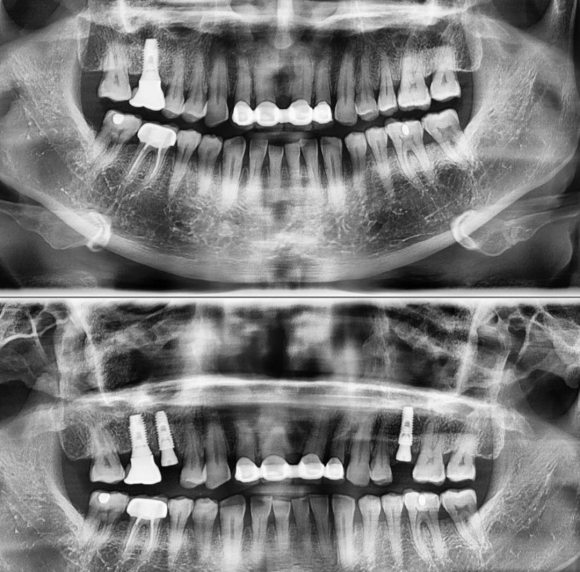

잇몸 질환으로 인한 통증으로 인해

치아를 발치 후 당일 즉시 식립 케이스 입니다.

심한 염증이 뼈를 많이 녹이지 않아서

건전한 뼈가 발치와 (치아를 빼고난 후 남은 치조골의 형태)를 360도 감싸고 있었고

협측 뼈가 3mm 이상 남아 있었기 때문에

당일 식립을 하고 뼈가 치유되기를 4개월 정도 기다린 후

임플란트 머리 보철이 올라갈 예정입니다.